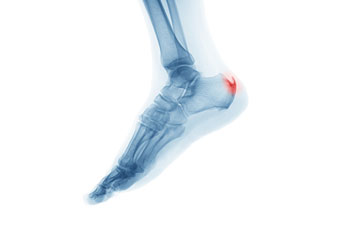

heel spur

A heel spur takes the form of a bony-like growth. This is due to a calcium deposit that extends between the heel bone and foot arch. They can grow up to half an inch in length; however, they may not be outwardly visible. Because heel spurs tend to grow, increasing the overall discomfort felt, it’s important that you seek professional help as soon as pain is experienced for early detection.